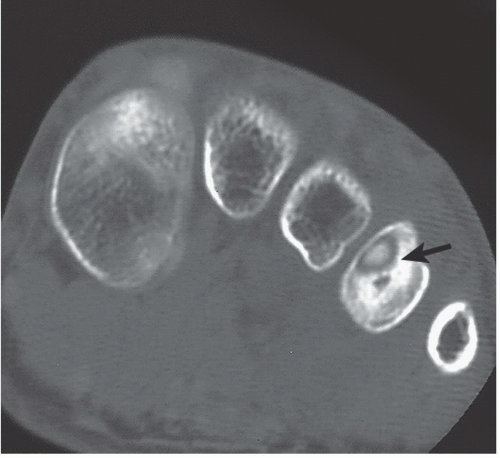

Ati questions that the professor asks you to complete musculoskeletal system ati module questions what is rheumatoid arthritis? Musculoskeletal System | Radiology Key